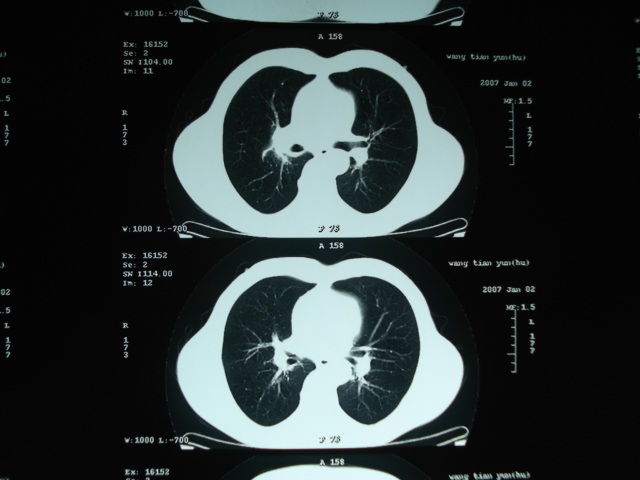

以下是引用狙击手在2007-4-18 20:17:00的发言:[br]原:2007/1/22号ct片:右肺上叶可见片状、云雾状高密度影,右肺上叶后段可见三角形高密度影,尖端指向肺门,右肺上叶后段支气管壁不规则增厚,管腔不规则增厚,纵隔未见肿大淋巴结.[br] 今ct:右肺上叶片状影增大,右肺上叶后段不张及右肺上叶后段支气管壁不规则增厚未见变化,右肺下叶背段支气管壁不规则增厚.[br] 如果考虑肺结核,但从临床证据看竟然没有一项支持肺结核,不知患者是否已经过正规抗结核治疗。没有的话,3个月了前后片看起来变化不大,似乎有不太符合肿瘤征象,不知患者是否抗炎治疗过,下叶支气管增粗还是要高度警惕,同意楼主意见,将常规病理,生化检查再做一遍。[br]

以下是引用狙击手在2007-4-18 20:17:00的发言:[br]原:2007/1/22号ct片:右肺上叶可见片状、云雾状高密度影,右肺上叶后段可见三角形高密度影,尖端指向肺门,右肺上叶后段支气管壁不规则增厚,管腔不规则增厚,纵隔未见肿大淋巴结.[br] 今ct:右肺上叶片状影增大,右肺上叶后段不张及右肺上叶后段支气管壁不规则增厚未见变化,右肺下叶背段支气管壁不规则增厚.[br] 如果考虑肺结核,但从临床证据看竟然没有一项支持肺结核,不知患者是否已经过正规抗结核治疗。没有的话,3个月了前后片看起来变化不大,似乎有不太符合肿瘤征象,不知患者是否抗炎治疗过,下叶支气管增粗还是要高度警惕,同意楼主意见,将常规病理,生化检查在做一遍。[br]